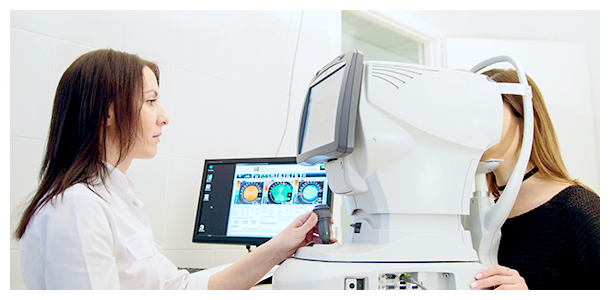

医疗美容(Facialmake-up,art of)是指运用药物、手术、医疗器械以及其他具有创伤性或者不可逆性的医学技术方法对人的容貌和人体各部位形态进行的修复...

整形的治疗范围主要是皮肤、肌肉及骨骼等创伤、疾病、先天性或后天性组织或器官的缺陷与畸形。治疗包括修复与再造两个内容。以手术方法进行自体的各种组织移植,也可采用异...